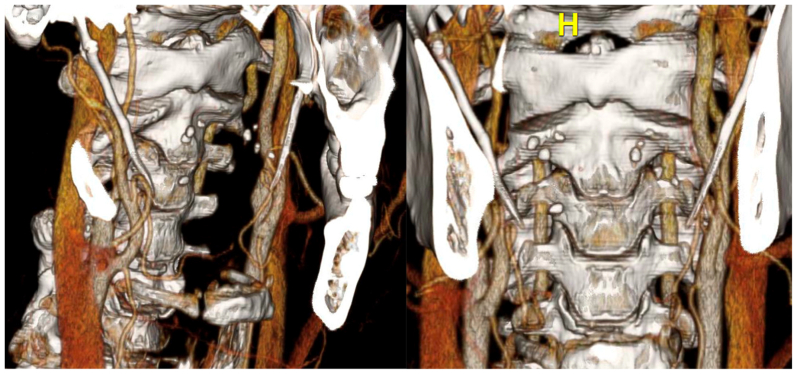

Fig 1.

Preoperative duplex ultrasound demonstrating a severely narrowed flow channel within the right (RT) internal carotid artery (ICA), with concern for possible occlusion in the proximal (P) ICA segment and a small flow channel observed distally in the mid-ICA segment (M).

Fig 3.

Computed tomography angiography (CTA) reconstruction demonstrating bony abnormality and degree of carotid artery stenosis.